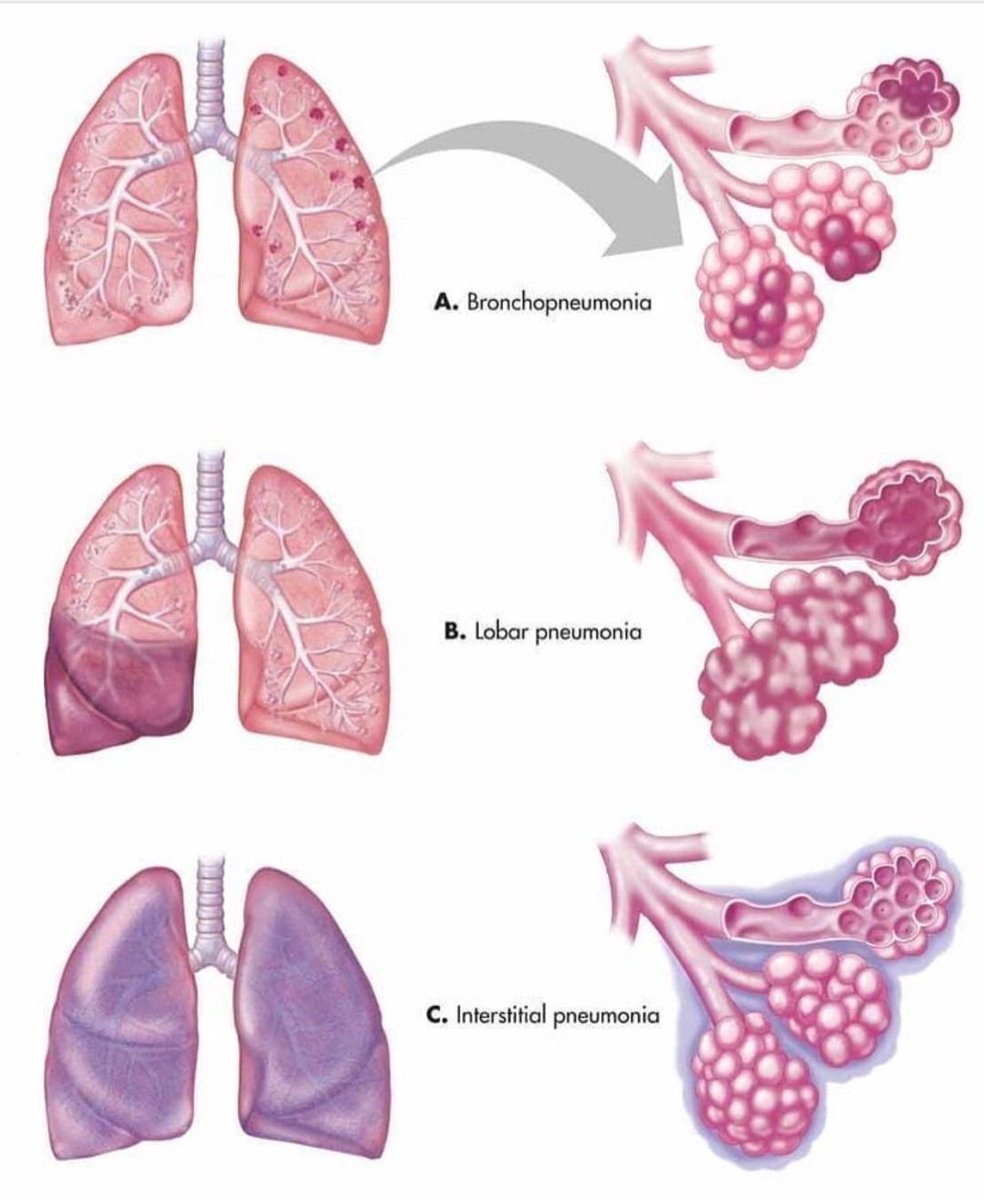

Пневмония - это серьезное заболевание легких, которое может быть вызвано различными причинами, включая бактериальные, вирусные и грибковые инфекции. Для того чтобы наглядно показать симптомы, диагностику и лечение этого заболевания, картинки могут быть очень полезны.

Картинки с симптомами пневмонии

В этом разделе представлены изображения, демонстрирующие различные симптомы пневмонии, такие как кашель, одышка, боль в груди и повышенная температура. Эти картинки могут быть использованы для обучения и презентаций в области медицины и здравоохранения.